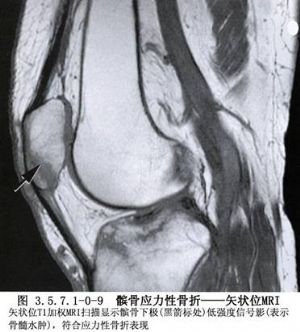

髌骨的解剖及髌骨骨折影像表现见下图(图3.5.7.1-0-1~3.5.7.1-0-10)。